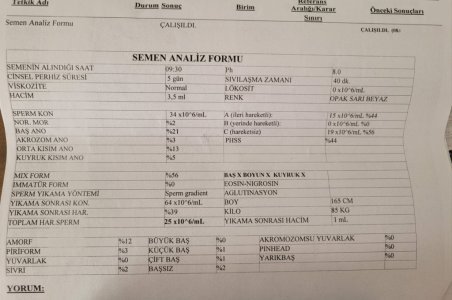

Semen analizi marmara eah'a ait.

Semen analizi marmara eah'a ait.